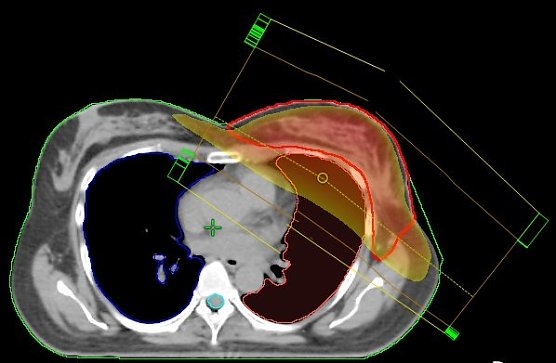

Normal: Stehfeldtechnik mit 2 Feldern (Standardtechnik); der Hochdosisbereich erfasst nicht nur das Zielvolumen (rote Kontur), sondern auch die umgebenden Risikoorgane (Lunge und Herzkranzgefäße), was zu Nebenwirkungen führen kann

Einzigartig in Nordhausen: VMAT-Bewegungsbestrahlungstechnik mit 2 Bögen (Nordhäuser Standardtechnik); der Hochdosisbereich erfasst ausschließlich das Zielvolumen und die umgebenden Risikoorgane werden geschont.